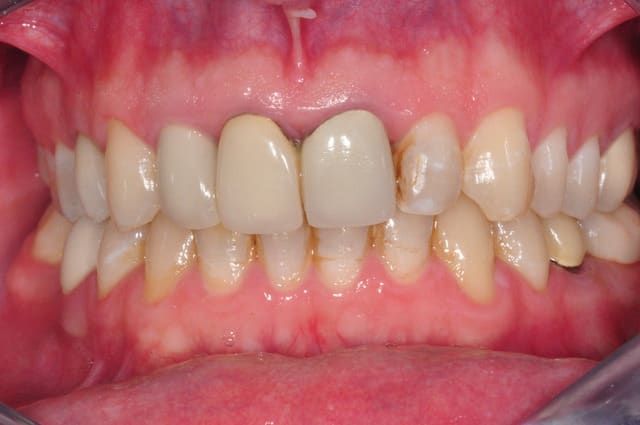

non en fait ma question porte sur l'état de surface de mes emax,

la coloration est présente depuis un bon moment et je n'en connais pas l'origine

je joins une photo avant traitement